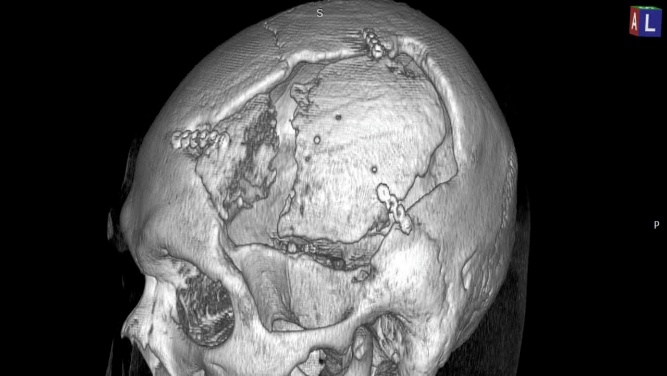

Vá khuyết hổng sọ bằng lưới Tiatan có sử dụng công nghệ 3D